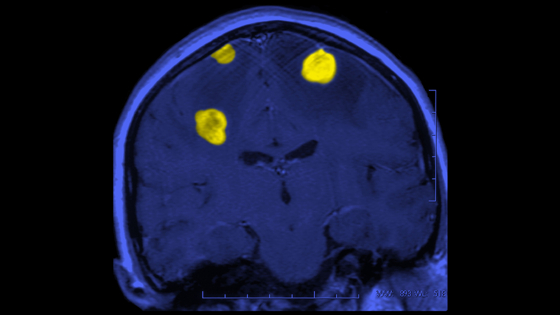

Исследование европейских ученых показало, что эффективной профилактикой опухолевых процессов в мозгу является употребление кофе и чая - об этом сообщил American Journal of Clinical Nutrition. Отметим, что ранее представители науки отстаивали теорию, что кофе и чай могут снижать риск развития нейродегенеративных патологий, в том числе болезней Альцгеймера и Паркинсона. В пользу ощутимого противоракового эффекта чая и кофе говорят результаты аналитической проверки данных масштабного опроса европейцев в рамках Европейского проспективного исследования раковых заболеваний и питания. Этот проект вобрал в себя информацию об образе жизни людей из десяти стран региона, собиравшуюся в течение восьми лет. По его итогам аналитики подтвердили наличие корреляции между регулярным употреблением чая и кофе и уменьшением вероятности развития опухоли мозга. Кофе и чай – напитки, доступные для многих людей. Таким образом, их употребление является оптимальным методом профилактики смертельно опасного заболевания, подчеркивают эксперты. Европейский проект, в частности, выявил у любителей кофе и чая положительный эффект этих напитков в отношении таких видов рака мозга, как глимома и менингиома. Употребление чая, например, снижало вероятность появления глиом на 34 процента. В свою очередь, исследователями, представляющими Istituto di Ricerche Farmacologiche Марио Негри в Милане, было установлено, что чай и кофе снижают риск глиобластомы – тяжелейшей разновидности рака мозга. Именно этот онкологический недуг убил популярную певицу Жанну Фриске. (ЧИТАТЬ ДАЛЬШЕ)